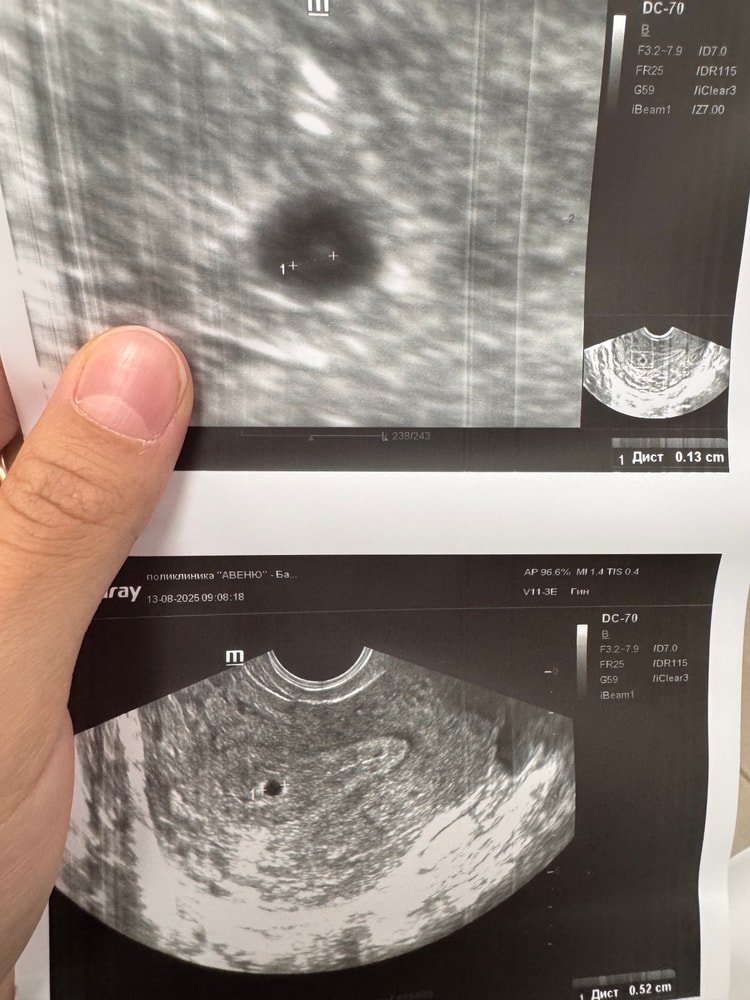

Выделения обычные светло желтые , но их как будто стало больше. И при этом ноет живот , но у меня жесткие запоры, поэтому возможно это кишечник. А может нет. По узи 11.09 была гематома 1х1см

сейчас срок 11н

Сейчас 10н5д , по самочувствию уже лучше становится. Тошнота вроде как прошла, начался жор😂 грудь также чувствительна . Постоянно мерзну. Вроде как сонливость уже не такая сильная. В 9н нашли гематому 1х1 , но она мне не мешает. Больше всего мне мешает мой кишечник, начались лютые запоры🫤🫤На скрининг записалась в 13.0 через пару недель. Сердечко

10 дней назад жм был 3мм(в 6н)

сегодня ктр 13мм, ПЯ 32мм, жм 5мм

большой ?